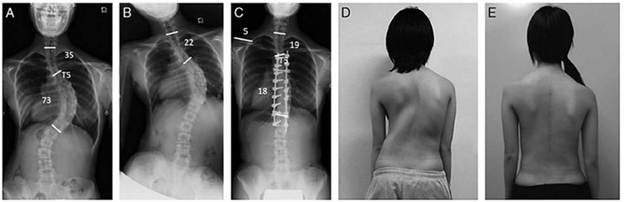

Нурууны хажуугийн мурийлт буюу сколиозыг Коббын өнцөгөөр хэмжих бөгөөд энэ нь 10°-аас их байгаа тохиолдолд сколиоз гэж тооцдог.

Хэрэв сколиозтой гэж үзэж байгаа бол өвчтнийг рентген шинжилгээнд илгээнэ. Босоо байрлалд хажуу ба урд талаас нь авсан багана нурууны бүтэн зурагт сколиозыг үнэлж үздэг. Хэсэгчлэн өвсан рентген зурагт мурийлт сайн ажиглагдахгүй байх талтай. Бас сурийлтын зэргийг тогтооход бэрхшээлтэй байдаг.

1-2 зэргийн сколиозын эмчилгээний ихэнх нь урьдчилан сэргийлэх, дасгал хийхэд чиглэгддэг. 3-р зэргийн сколиозын үед зориулалтын корсет буюу бэхэлгээ зүүх, хурдан даамжирч байвал мэс засал хийх нь тохиромжтой байдаг. 25 хэмээс дээш муруйлттай, нас бие гүйцээгүй өвчтөнүүдэд бэхэлгээг нэн даруй эхлэх хэрэгтэй.

45-50 хэмээс дээш муруйтай өсч буй өсвөр насныхан сколиозыг хянах, засахад бусад эмчилгээний хэлбэрүүд үр дүнгүй байдаг тул мэс заслын эмчилгээ шаарддаг. 50-55 хэмээс дээш муруйлттай, ясны хувьд боловсорсон хүмүүс муруйлт үргэлжлэх эрсдэлтэй тул мэс заслын эмчилгээнд хамрагдах шаардлагатай.